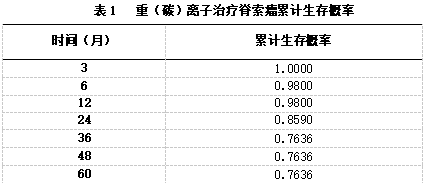

对50例未接受手术治疗脊索瘤患者进行生存分析,其随访时间(0~64)个月。使用K-M法进行生存分析,治疗结束时累计生存概率为1.0000,治疗结束后12、24、36个月的累计生存概率分别为0.9800、0.8590、0.7636。(见表1)

图1 治疗结束时到治疗结束后60个月生存曲线图